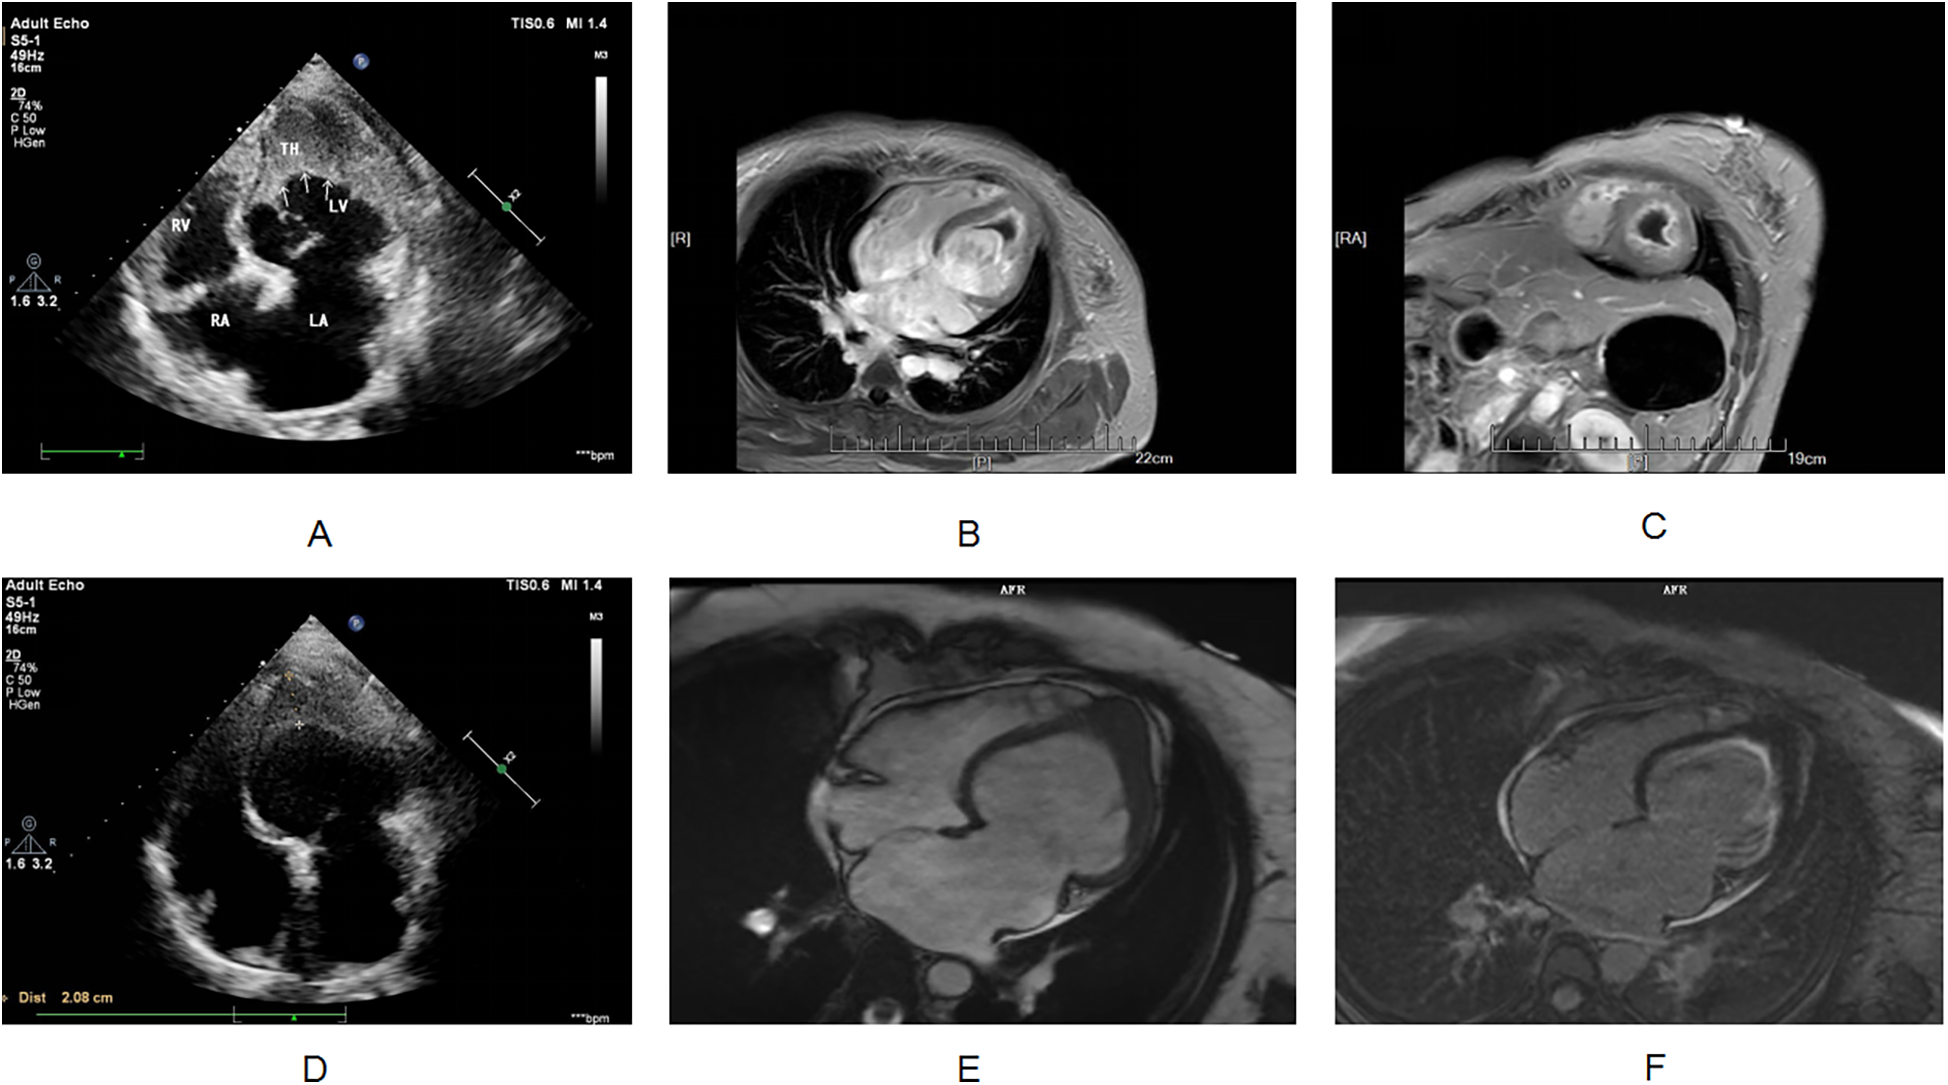

The etiology of her heart failure remains under investigation. Potential causes included coronary artery disease, valvular heart disease, hypertension, primary or secondary cardiomyopathy, congenital heart disease, pericardial disease, and others (5). The above research indicated that the patient was less likely to have atherosclerotic disease and has no history of hypertension. Cardiac ultrasound showed abnormal left ventricular structure. It is unclear whether there is valvular heart disease, cardiomyopathy, pericardial disease or congenital heart disease. Therefore, the patient needed to undergo another echocardiogram and CMR, as necessary. The next step focused on investigating the causes of both the suspected cardioembolic event and heart failure. Echocardiogram revealed the following findings: left atrial anterior-posterior diameter 41 mm, left ventricular end-diastolic diameter 57 mm, right atrial long diameter 53 mm, right atrial transverse diameter 47 mm, right ventricular anterior-posterior diameter 23 mm, left ventricular ejection fraction 34%, pulmonary artery systolic pressure 44 mmHg, left ventricular mid- and lower-segment thrombus (approximately 36 × 34 mm; Figure 2A), decreased left and right ventricular wall movement, decreased left ventricular systolic and diastolic function, decreased right ventricular systolic function, and a small amount of pericardial effusion. It did not detect any congenital structural abnormalities, valvular heart disease, cardiomyopathy, or pericardial disease.

Figure 2

(A) Transthoracic echocardiography shows apical occlusion and numerous mid to high echogenic masses in the lower left ventricular cavity. (B,C) Cardiac magnetic resonance imaging shows occlusion of the apical segment of the left ventricle, and myocardial delayed enhancement imaging shows diffuse enhancement lesions beneath the endocardium of the left ventricle. The signal of the cardiac mass is not enhanced. (D) After hormone combined with warfarin treatment, apical occlusion was still observed on transthoracic echocardiography, and the number of hyperechoic masses in the lower left ventricular cavity decreased compared to before. (E,F) After one year of treatment with imatinib, cardiac magnetic resonance imaging showed apical occlusion, myocardial delayed enhancement imaging showed subendocardial enhancement in the left ventricle, and the cardiac mass completely disappeared.

While her recent history included an infection, it was not suggestive of fulminant or severe myocarditis. Therefore, further investigation was necessary to clarify the cause of the dilated cardiomyopathy, particularly considering her elevated eosinophil count on routine blood tests. Eosinophilic syndrome is independently associated with ventricular thrombus formation, and the investigation was focused on this possibility. Eosinophils store various biologically active molecules in their granules. When extensively activated, these eosinophil-derived (toxic) substances can damage nearby tissues, leading to local inflammation, cytotoxicity, thromboembolic complications, and/or fibrosis (8). Cardiac involvement by eosinophils can manifest as either acute fulminant myocarditis (acute necrotizing cardiomyopathy) or chronic restrictive cardiomyopathy (Loeffler's endocarditis) (9). Given this patient's situation, Loeffler endocarditis emerged as a strong possibility as it could explain both the impaired heart function and the ventricular thrombus. The gold standard for diagnosing Loeffler endocarditis is an endocardial muscle biopsy; however, this procedure is invasive and not readily accepted by patients. CMR offers an alternative, providing a non-invasive imaging biopsy that can reveal inflammation, apical thrombosis, and fibrotic granulation tissue (10). To further investigate the cause of her condition, CMR was performed on the fourth day of admission. The results suggested Loeffler endocarditis involving the left ventricular myocardium, with apical occlusion thrombus formation (Figures 2B,C).

After identifying the cause, we developed a treatment plan. Currently, there are no clear evidence-based guidelines or consensus statements regarding the treatment of Loeffler's endocarditis. Existing case reports suggest that steroids are effective in some patients, while secondary immunosuppressants are effective in others. Steroid use was higher in patients with HES-induced steroid drugs (9). For patients with life-threatening eosinophilic complications, high-dose corticosteroids (at least 1 mg/kg of prednisone daily) are typically used for a short course (1). Therefore, we treated the patient with 80 mg of methylprednisolone for four days, followed by anticoagulation with 2.5 mg of warfarin. The patient's chest tightness and suffocation symptoms significantly reduced, and the amount of methylprednisolone gradually decreased. After one week of treatment, follow-up cardiac ultrasound was performed, showing an increased left ventricular ejection fraction of 50%. Following discharge, her treatment continued with oral warfarin and prednisone. Weekly INR monitoring ensured a range of 2.0–3.0. The prednisone dose was 50 mg with a reduction of 10 mg/week. After 20 days of treatment, follow-up cardiac ultrasound showed a normal left ventricular ejection fraction (54%). However, the left side of the heart remained enlarged. Additionally, a left ventricular thrombus was still present. Subsequently, multiple cardiac ultrasound examinations showed a decrease in the volume of the cardiac mass, although it did not completely disappear (Figure 2D). As expected, her eosinophil count gradually decreased after treatment, reaching 0 (Figure 3). However, the persistence of the cardiac mass led us to question its nature and we speculated that granulation tissue or other tissue types might be mixed with the thrombus. Therefore, the prednisone dosage was gradually reduced until discontinued, and imatinib was added. After one year of treatment with imatinib, the patient's cardiac mass completely disappeared (Figures 2E,F).